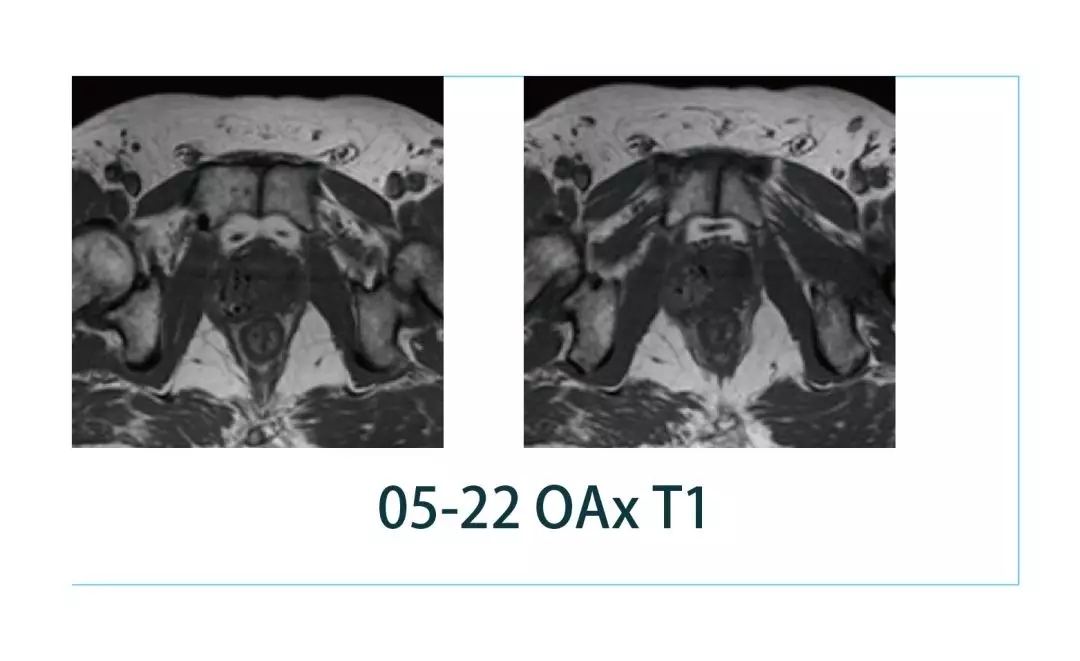

【朗润影像档案】20190308磁共振影像病例结果讨论